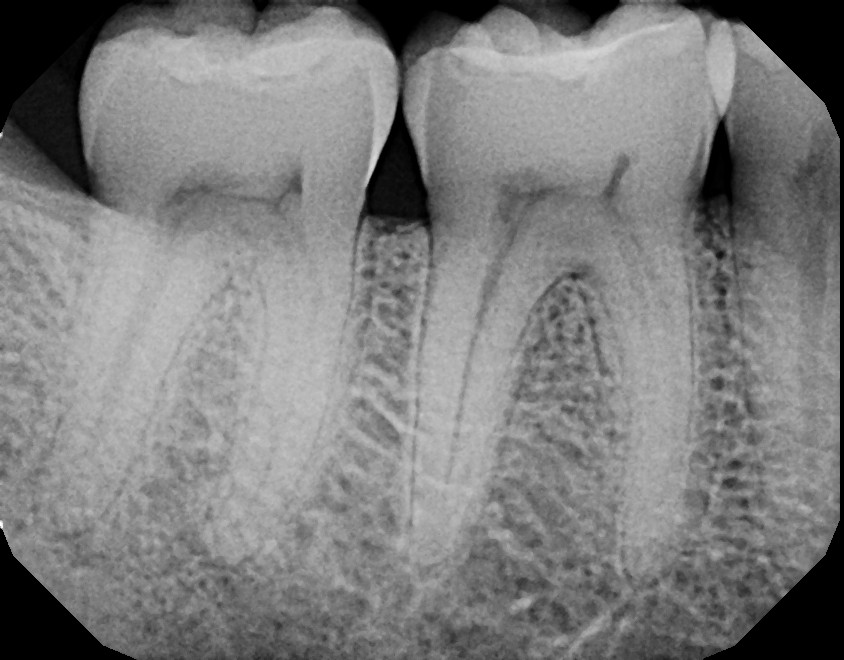

This second mandibular molar (tooth #31) never had any fillings in the past but started feeling sensitive to hot, cold, and bite. Upon examination, the tooth revealed a crack on the crown portion which required a root canal and crown. If this patient did not notify their dentist to refer them for an examination with an endodontist, tooth extraction would eventually become the only alternative. With proper treatment, this patient kept their tooth, saved a lot of money avoiding an implant, and had a dental night guard fabricated because they were a grinder/clencher who was damaging their teeth unknowingly.